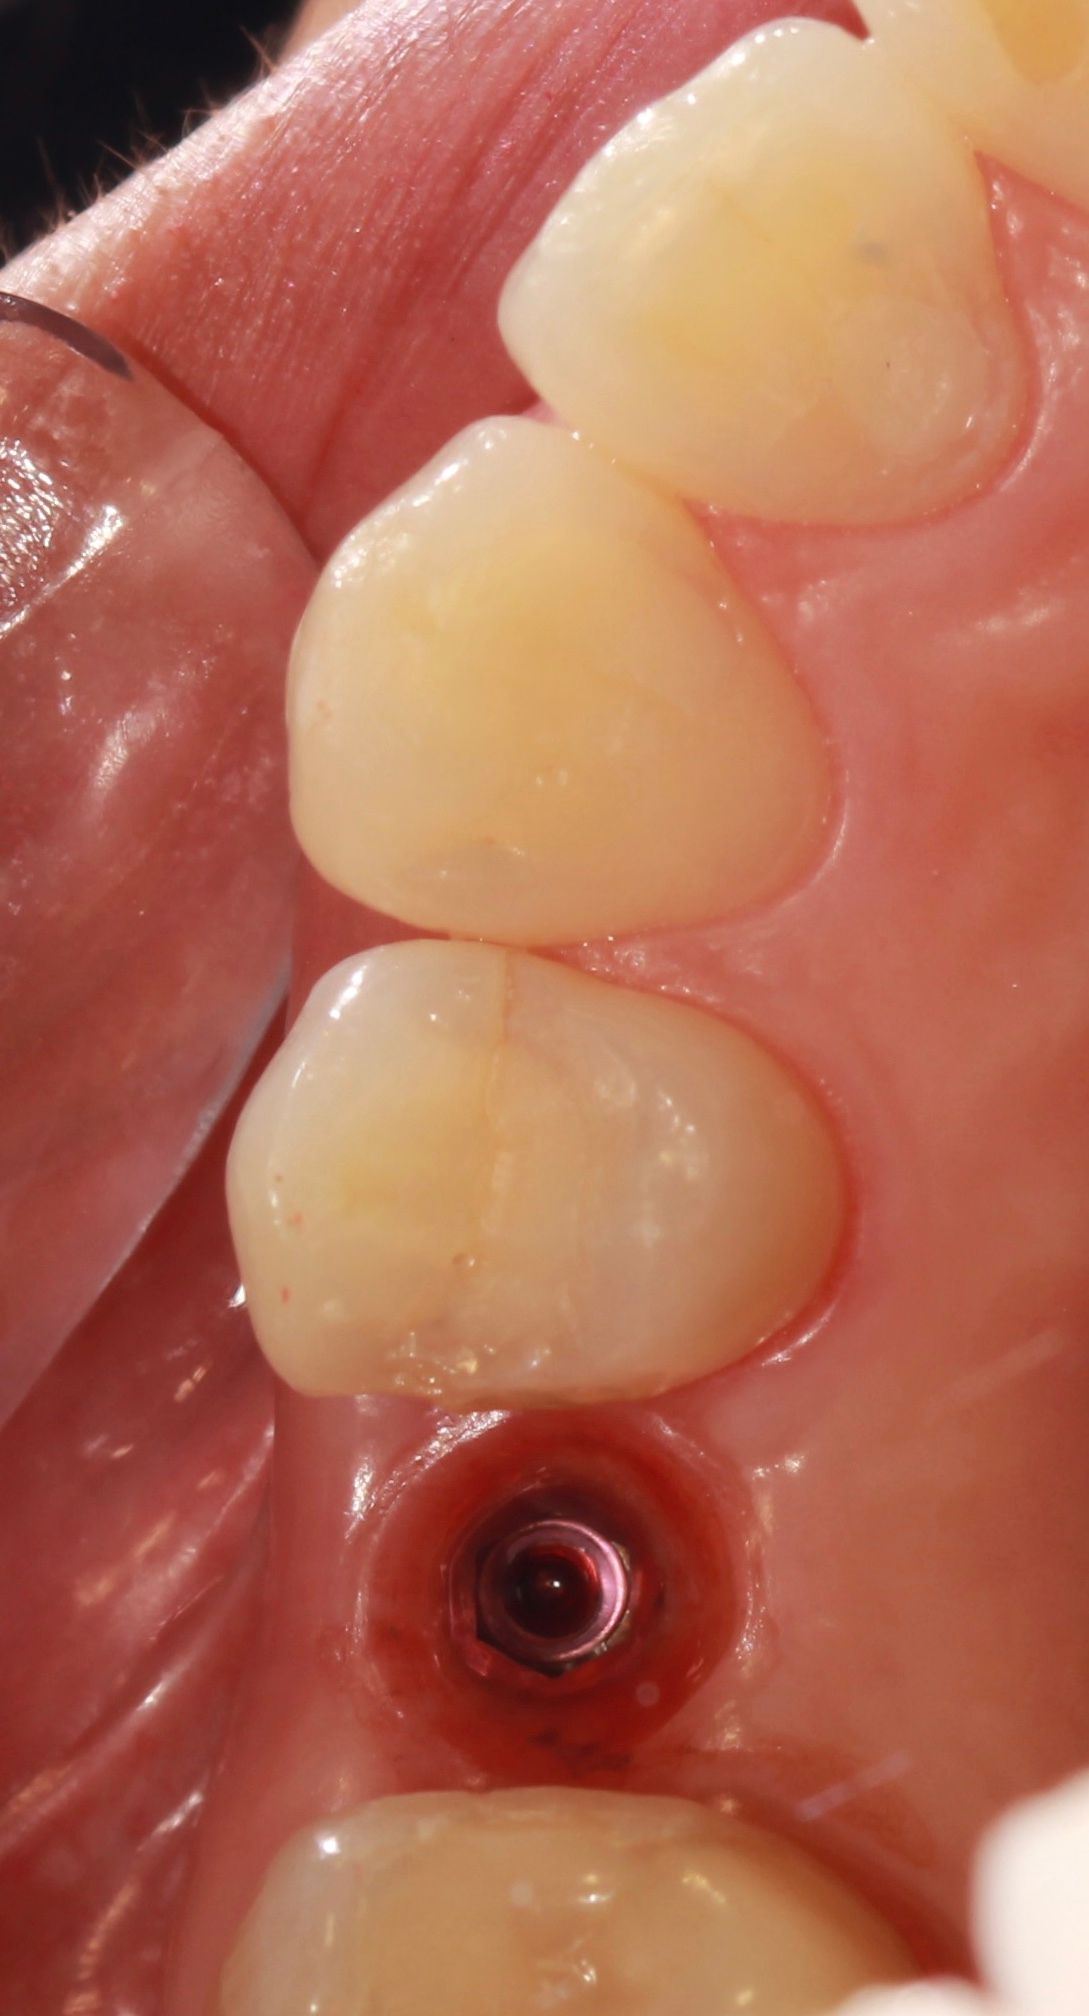

Especialista en Implantología Oral quirúrgica y protesica, cédula de especialidad: 12411844

La especialidad en Implantología Oral se enfoca en sustituir órganos dentarios perdidos por implantes dentales mediante una fase quirúrgica y una fase protesica y de esta manera devolver la función, estetica y confort dental del paciente.